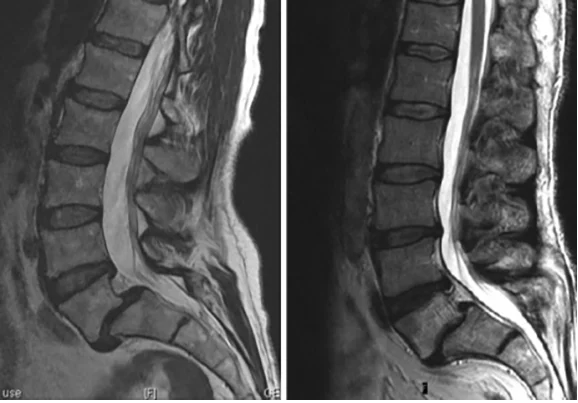

Spondylolisthesis

• Spondylolisthesis is the forward translation of a vertebra, most commonly L5’. They can be graded as I to IV depending on severity